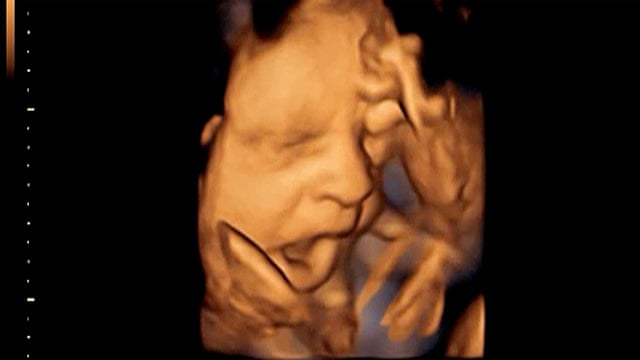

Baby Yawning In Womb

Letting babies sleep long. Biology is a wondrous science that inspires us to discover more about the world around us. And thanks to 4D ultrasound technology little ones can be seen yawning stretching and even sucking their thumb at this age in the womb.

Babies will typically exhibit a startled look. These problems may include. Yawning begins by 9½ weeks60 By 10 weeks. While science may not have the answers to every question some biology questions are answerable. Babies will typically exhibit a startled look. The Moro or startle reflex causes your baby to extend their arms legs and fingers and arch when startled by the feeling of falling a loud noise or other environmental stimuli. The art of the yawn has been mastered by your baby along with hiccupping which you may feel soon too. 18 week fetus images. Watch for sleep cues.